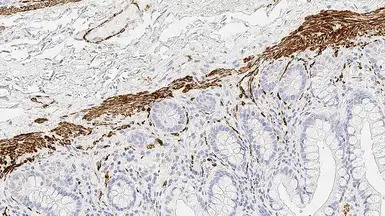

IHC-P analysis of human bowel tissue using GTX01930 Desmin antibody [DE-R-11]. Note cytoplasmic staining of smooth muscle containing cells.